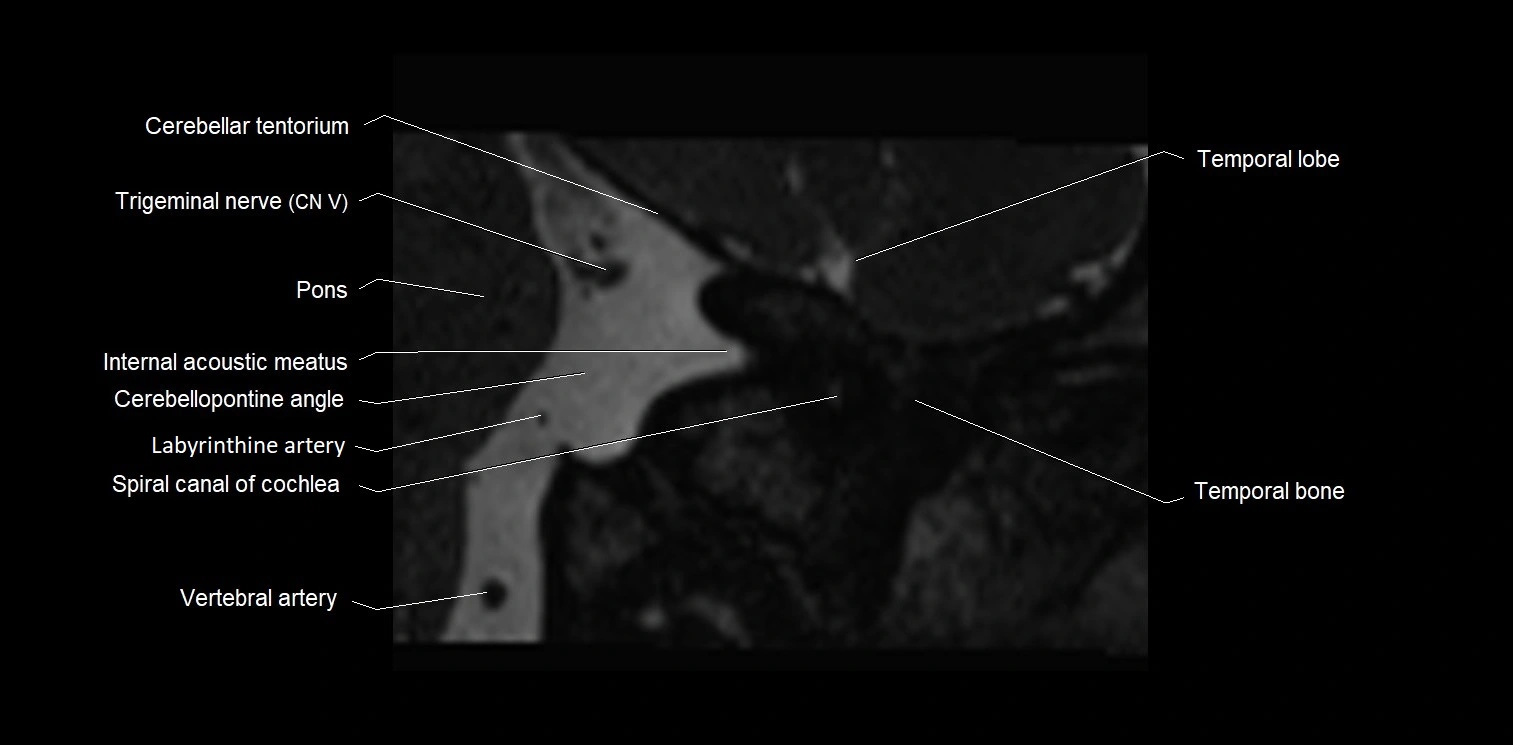

MRI images

image